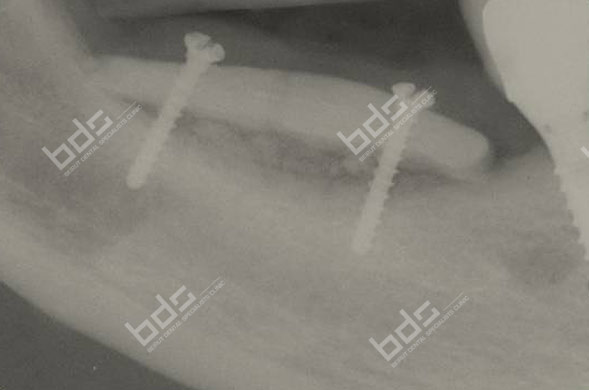

Wisdom teeth extraction

Wisdom teeth, also known as third molars, are the last teeth to erupt in your mouth. This generally occurs between the ages of 17 and 25, a time of life that has been called the “Age of Wisdom”

Impacted teeth can cause pain during their eruption , infection or damage to the adjacent teeth or roots

More serious problems may occur if the sac surrounding the impacted tooth becomes inflamed , fills with fluid and enlarges to form a cyst. As the cyst grows it may hollow out the jaw increasing the risk of jaw fracture or seriously damage adjacent teeth and surrounding bone . As the cyst expands, more serious surgical procedure may be required to remove it with the risk of damaging the dental nerve or causing jaw fracture

In general, earlier removal of wisdom teeth before root formation is a less complicated procedure and is recommended by the American Association of Oral & Maxillofacial Surgeons if the teeth have no chance to erupt .This approach helps preventing future problems and ensures optimal healing.

Depending on the nature of your case, wisdom tooth extractions are performed under local anesthesia or intravenous sedation. Our doctors will speak to you before the surgery and answer any questions you have. After surgery it is common to experience swelling and discomfort . Pain killers and anti-inflammatory medications can help in the control of these post operative events.